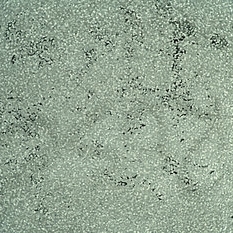

Slide 7-30

Feb 25 2019 by Lancaster Course in Ophthalmology

Pleomorphism, rather than polymorphism, characterizes a malignant lymphoma.

Condition/keywords: lymphoma, pleomorphism